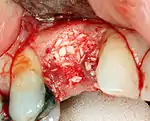

Hard tissue reconstruction

If bone width is inadequate it can be regrown using either artificial or cadaveric bone pieces to act as a scaffold for natural bone to grow around.

For an implant to osseointegrate, it needs to be surrounded by a healthy quantity of bone. In order for it to survive long-term, it needs to have a thick healthy soft tissue (gingiva) envelope around it. It is common for either the bone or soft tissue to be so deficient that the surgeon needs to reconstruct it either before or during implant placement.[32]:1084

Hard tissue (bone) reconstruction

Bone grafting is necessary when there is a lack of bone. Also, it helps to stabilize the implant by increasing survival of the implant and decreasing marginal bone level loss.[41] While there are always new implant types, such as short implants, and techniques to allow compromise, a general treatment goal is to have a minimum of 10 mm (0.39 in) in bone height, and 6 mm (0.24 in) in width. Alternatively, bone defects are graded from A to D (A=10+ mm of bone, B=7–9 mm, C=4–6 mm and D=0–3 mm) where an implant's likelihood of osseointegrating is related to the grade of bone.[42]:250

To achieve an adequate width and height of bone, various bone grafting techniques have been developed. The most frequently used is called guided bone graft augmentation where a defect is filled with either natural (harvested or autograft) bone or allograft (donor bone or synthetic bone substitute), covered with a semi-permeable membrane and allowed to heal. During the healing phase, natural bone replaces the graft forming a new bony base for the implant.[38]:223